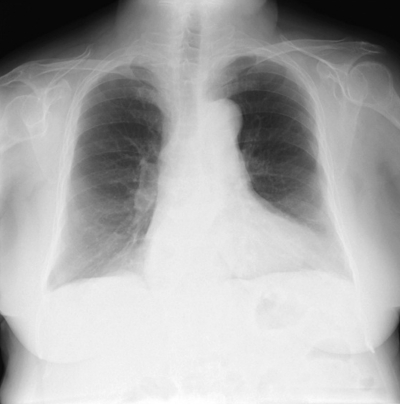

82歳の女性。買い物に行くと動悸と息切れがあり、NYHA分類はⅡ度の慢性心不全と診断されている。かかりつけ内科のある病院歯科を受診したところ埋伏智歯周囲に囊胞形成があり、手術を検討することとなった。同病院で撮影された胸部エックス線写真を術前評価の資料とした。胸部エックス線写真を別に示す。

特徴的な所見はどれか。1つ選べ。

a. 胸郭の変形

b. 心陰影の拡大

c. 肺血管陰影の増強

d. 肺野透過性の亢進

e. 肺野のすりガラス様陰影